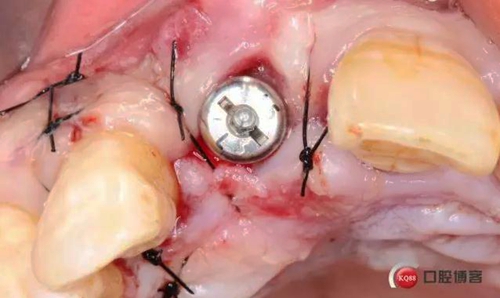

術(shù)后縫合